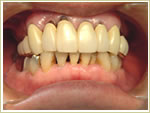

59歳 男性 インプラント埋入数:12本 |

治療後 |